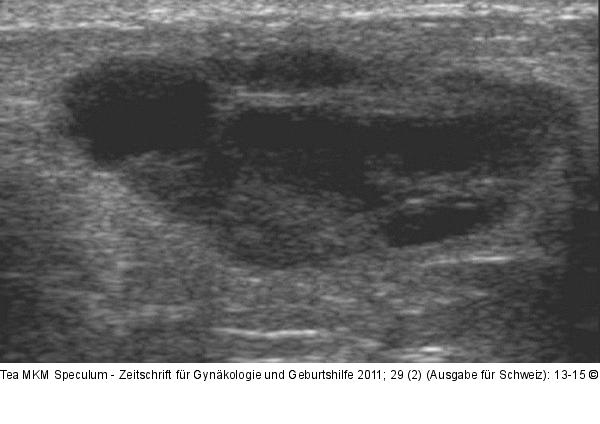

Abbildung 3: Komplexe Mammazyste Komplexe Mammazyste |